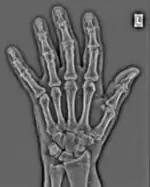

The essence of this approach is that it can be used to produce a range of image processing effects by enhancing and/or suppressing features in the 2D-FFT and then converting the result back into the spatial domain using the IFT, as illustrated in Figure 1.28. Such image manipulations are considered in more detail in a later chapter. Note that the form of image processing demonstrated in the figure is for purely illustrative purposes and bears no direct medical significance.

![]() Fig. 1.28(a): A radiograph of the wrist. | ![]() Fig. 1.28(b): The wrist radiograph processed by attenuating periodic structures of size between 1 and 10 pixels. |

![]() Fig. 1.28(c): The wrist radiograph processed by attenuating periodic structures of size between 5 and 20 pixels. | ![]() Fig. 1.28(d): The wrist radiograph processed by attenuating periodic structures of size between 20 and 50 pixels. |